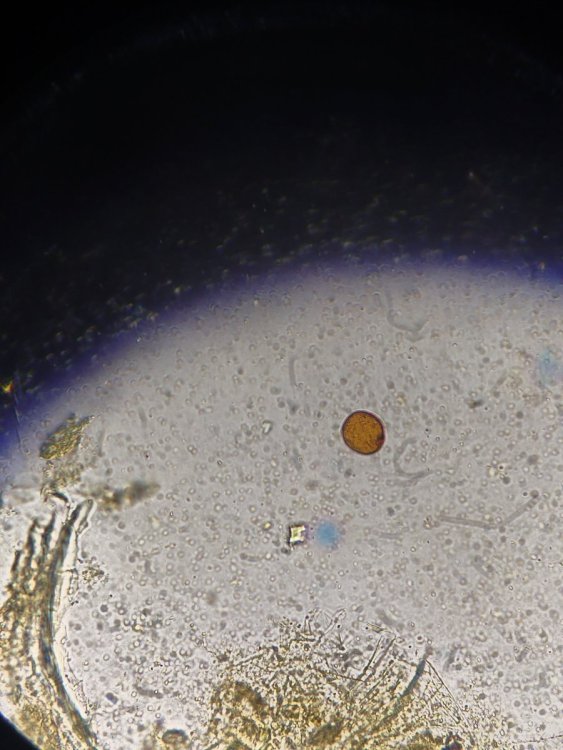

Здравствуйте. Помогите, пожалуйста, разобраться. Волнистый попугай, девочка, 3 года 5 месяцев. Лечили мегабактериоз, на вчерашней микроскопии ни одной мегабактерии, однако рвота и непереваренные зерна в помете остаются. Сделали рентген, орнитологи в замешательстве, у каждого свое отличное мнение по поводу преджелудка , печени и новообразовании в лёгких. В помете также нашли много пыльцы, однако возможно , что это глисты. Снова не понятно. Помогите , пожалуйста, разобраться с рентгеном и микроскопией. Фото прикладываю.